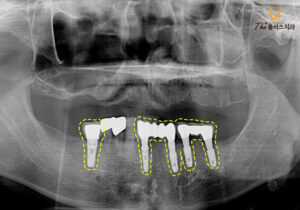

엑스레이 사진을 보시면

노란색의 점선은

현재 환 자분의 잇몸뼈 높이로,

염증으로 인해 잇몸뼈가 소실되어

많이 내려가 있는 모습입니다.

이미 아래쪽 왼쪽과 오른쪽의

큰 어금니들은 상실되었고,

남아있는 치아들도 치료가 필요하였습니다.

아래 앞니 부위에는

뿌리 주위로 까맣게 염증이 보이고,

양쪽의 큰 어금니들이 상실되어

음식을 저작할 때 앞니로만 사용하여

영향이 간 것으로 판단되었는데요.